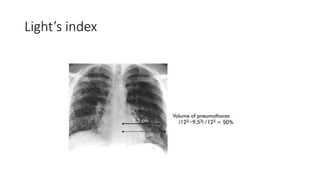

Light’s index

ACCP 2001 BTS 2010